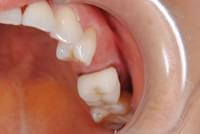

写真は、抜歯後の口腔内の写真です。見るからに、骨が少なく、陥凹してしまっていました。